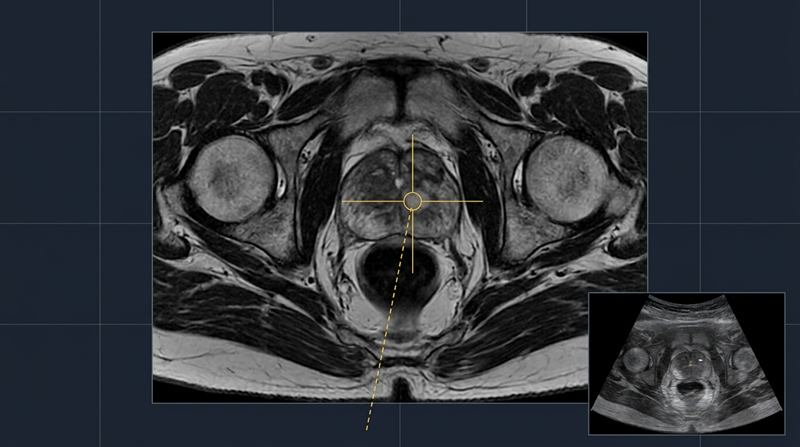

Dr Raji Kooner successfully completed the first pure single port robotic procedure in NSW — a true single-incision approach without any assisting ports — with support from Dr Ryan Nelson (USA).